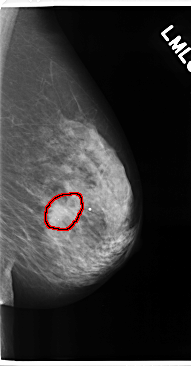

FILE: C_0175_1.LEFT_CC.OVERLAY

TOTAL_ABNORMALITIES 1

ABNORMALITY 1

LESION_TYPE MASS SHAPE IRREGULAR MARGINS ILL_DEFINED

ASSESSMENT 5

SUBTLETY 4

PATHOLOGY MALIGNANT

TOTAL_OUTLINES 1

BOUNDARY